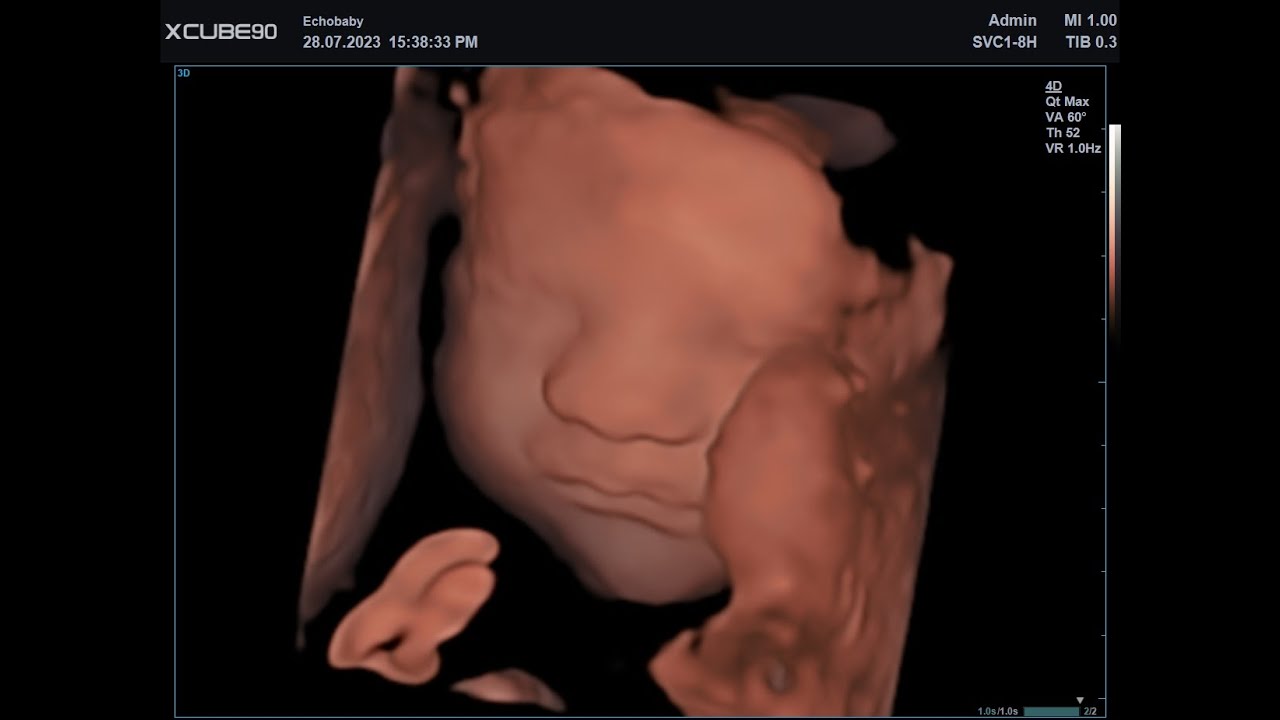

Echo Baby 31 Weken Zwanger 3D Foto's

Echo Baby 31 Weken Zwanger 3D Foto's. Op sommige foto's van deze 3D echo 31 weken zitten er handjes en voetjes bij in beeld, maar kijk eens hoe mooi je dit kindje kan zien.

Gemaakt bij Echobaby in Lommel